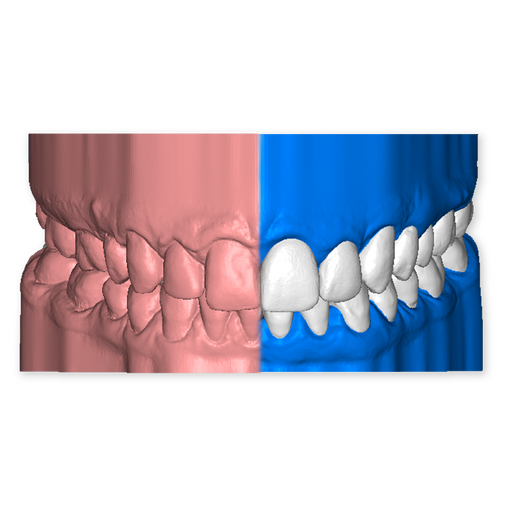

The DSD Interdisciplinary is a digital wax up of the upper and lower arches, designed considering a facially-driven, clinical and functional analysis of the patient.

It is our most comprehensive planning option, and includes all the 3D treatment simulations needed for each case, such as ortho, perio, implants, grafts and orthognathic surgery.

Our 3D simulations showcase facilitate a deeper understanding of the required procedures. This leads to the creation of a broader treatment plan and enables a more efficient communication with your patients.